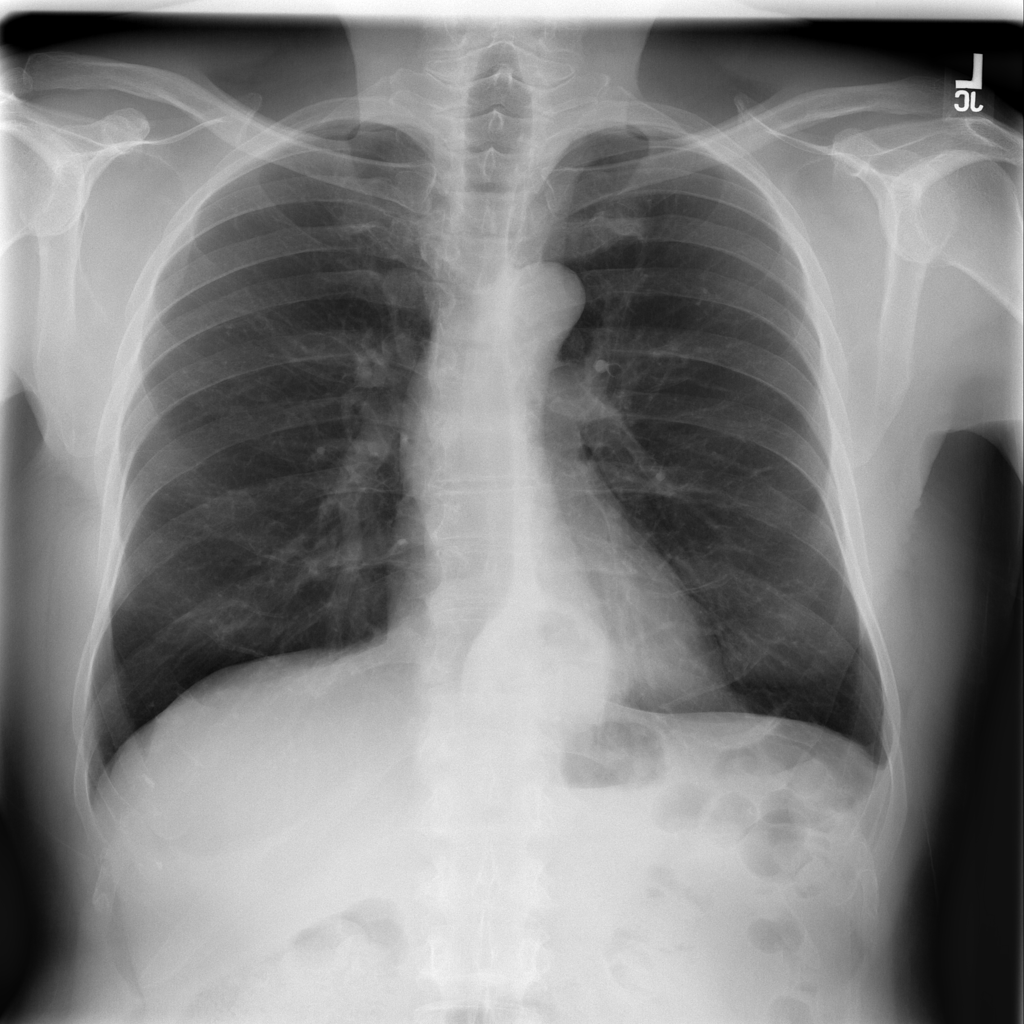

PAT-4F7E · IMG-000Hernia

PAT-4F7E · IMG-000

PA